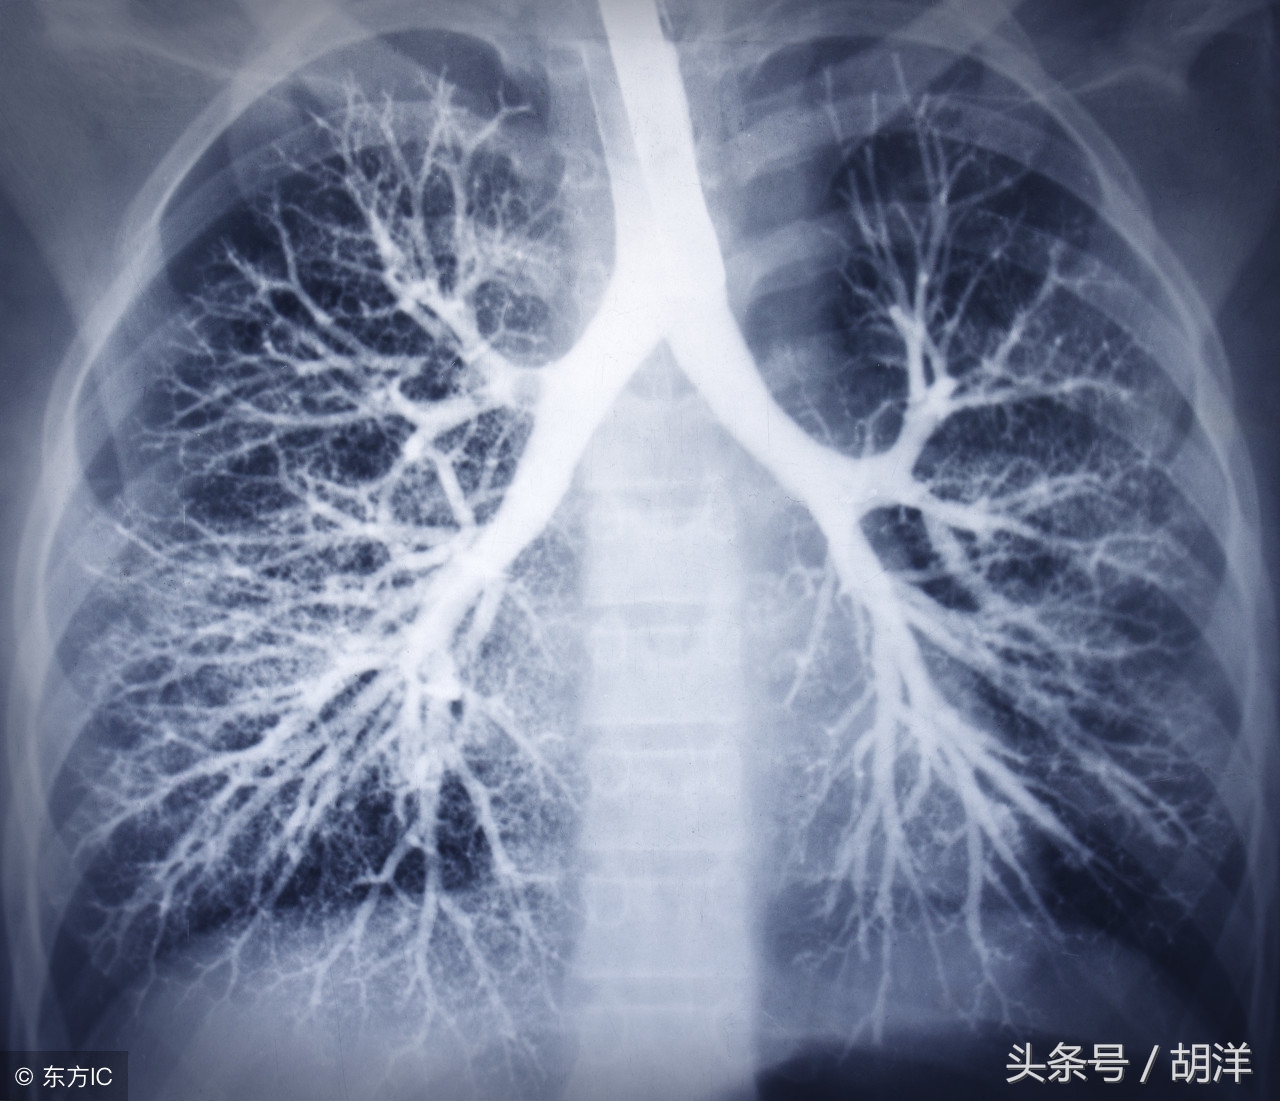

咳血又称咯血,是呼吸科一个比较严重的症状,由于其可能提示肺部肿瘤等严重疾病而受到重视,但事实上在引起咯血的病因中,肺部恶性肿瘤所占的比例并不是很大,但很多人因咯血而焦虑异常,特别是咯血久治不愈情况下,更加令人无法正常的生活和学习,那么哪些疾病可能导致反复发作痰中带血或者咳出满口鲜血呢?